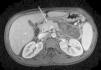

El lupus eritematoso sistémico (LES) es una enfermedad sistémica multiorgánica que puede producir prácticamente cualquier síntoma. Dentro de las formas de inicio es extraordinariamente infrecuente el desarrollo de pancreatitis. Se presenta el caso de una niña de 12 años que acude a urgencias por dolor abdominal intenso en el mesogastrio e hipocondrio, de 48h de evolución, y vómitos biliosos incoercibles. En la anamnesis refiere artralgias en rodillas y hombros, astenia, pérdida de peso desde hace 6 semanas, exantema malar y fotosensibilidad de 15 días de evolución. No refiere ingesta de fármacos, traumatismo abdominal o litiasis. En urgencias, se aprecia defensa en el hemiabdomen superior, con elevación de la amilasa (2.433 U/l), la creatinina (1,66mg/dl) y la urea (114mg/dl), por lo que, con el diagnóstico de pancreatitis e insuficiencia renal aguda (IRA), es trasladada a nuestro centro. Al ingreso su peso es de 53,3kg y sus constantes son normales. Además del dolor abdominal, presenta un exantema malar papular bien definido, sin lesiones orales ni alopecia, y artritis de todas las articulaciones interfalángicas proximales de las manos. En la analítica destaca la elevación de la amilasa y lipasa séricas, y la presencia de linfopenia (780/μl), hipocomplementemia (C3 42mg/dl, C4 8mg/dl), positividad de ANA (1/640), de anticuerpos anti-ADN (1/64) y cilindruria. La IRA se filia como prerrenal y la pancreatitis se maneja conservadoramente, iniciando tolerancia por vía oral con éxito 5 días después del ingreso. En la ecografía inicial se observa un aumento del tamaño del páncreas, con hipoecogenicidad periférica compatible con necrosis difusa, y 2 colecciones, de 6,2×3cm y 4,6×1cm, en el tercio distal del cuerpo y cola, hallazgos confirmados en una RM realizada posteriormente(fig. 1). Una vez resuelta la IRA, se inicia tratamiento con bolos diarios de 1g de metilprednisolona (MP) IV durante 3 días consecutivos, seguido de la administración de prednisona por vía oral (7,5mg/día), bolos semanales de 750mg de MP e hidroxicloroquina (200mg/12h), con una magnífica respuesta clínica (SLEDAI [Systemic Lupus Erythematosus Disease Activity Index] inicial 12 puntos, al alta 4 puntos), por lo que es dada de alta y controlada ambulatoriamente.